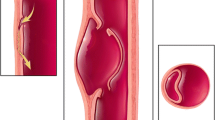

Acute type B aortic dissection results in an intense inflammatory process and the development of complex hemodynamics that interrelate the true and false lumens [4, 5]. The disease is dynamic, particularly in this phase and changeable behavior of the intimal flap, extension of the dissection and expansion of the false lumen are possible. This can lead to contained or free rupture of the aorta, organ and/or limb malperfusion, early false lumen expansion, resistant hypertension and uncontrollable pain [6]. Dissections with these features are considered to be complicated and endovascular intervention is indicated. Dissections without these features are considered to be uncomplicated and are currently treated with best medical therapy [7]. The boundary between complicated and uncomplicated dissection is, however, blurred and if anatomically suitable, pre-emptive endovascular treatment has been advocated in uncomplicated dissections as a viable alternative to medical treatment alone [8]. There are, however, considerable risks associated with endovascular repair, such as stroke and paraplegia and careful consideration should be given before its use in all cases [9].

Transesophageal echocardiography (TEE) has a high accuracy for the diagnosis of aortic dissection and provides excellent anatomical and functional imaging of the descending thoracic aorta (Fig. 4; [10, 24]). In type B dissections it can be used to accurately recognized true and false lumens, proximal and distal reentry tears and can show the hemodynamic behavior of the intimal flap. Its main limitation is that no images are acquired below the diaphragm and because it is a semi-invasive procedure sedation is required. In the acute phase of a type B dissection its main role is probably for intraoperative assessment when endovascular treatment is required [25]. The images can be used to ensure the device is in the true lumen and positioned to cover the dominant entry tears. False positives can occur because of linear reverberation images, particularly in the ascending aorta. There are also blind areas, which limit assessment of the distal ascending aorta and proximal arch. The adjunct of color Doppler can facilitate identification of the true and false lumens.

Transesophageal echocardiography (TEE) imaging demonstrating the infolding and unwinding (arrows) of the intimal flap at the level of the ascending aorta (a, b), and fluctuation of the intimal flap at the level of the descending aorta during the cardiac cycle (c, d, e) (TL true lumen, FL false lumen)